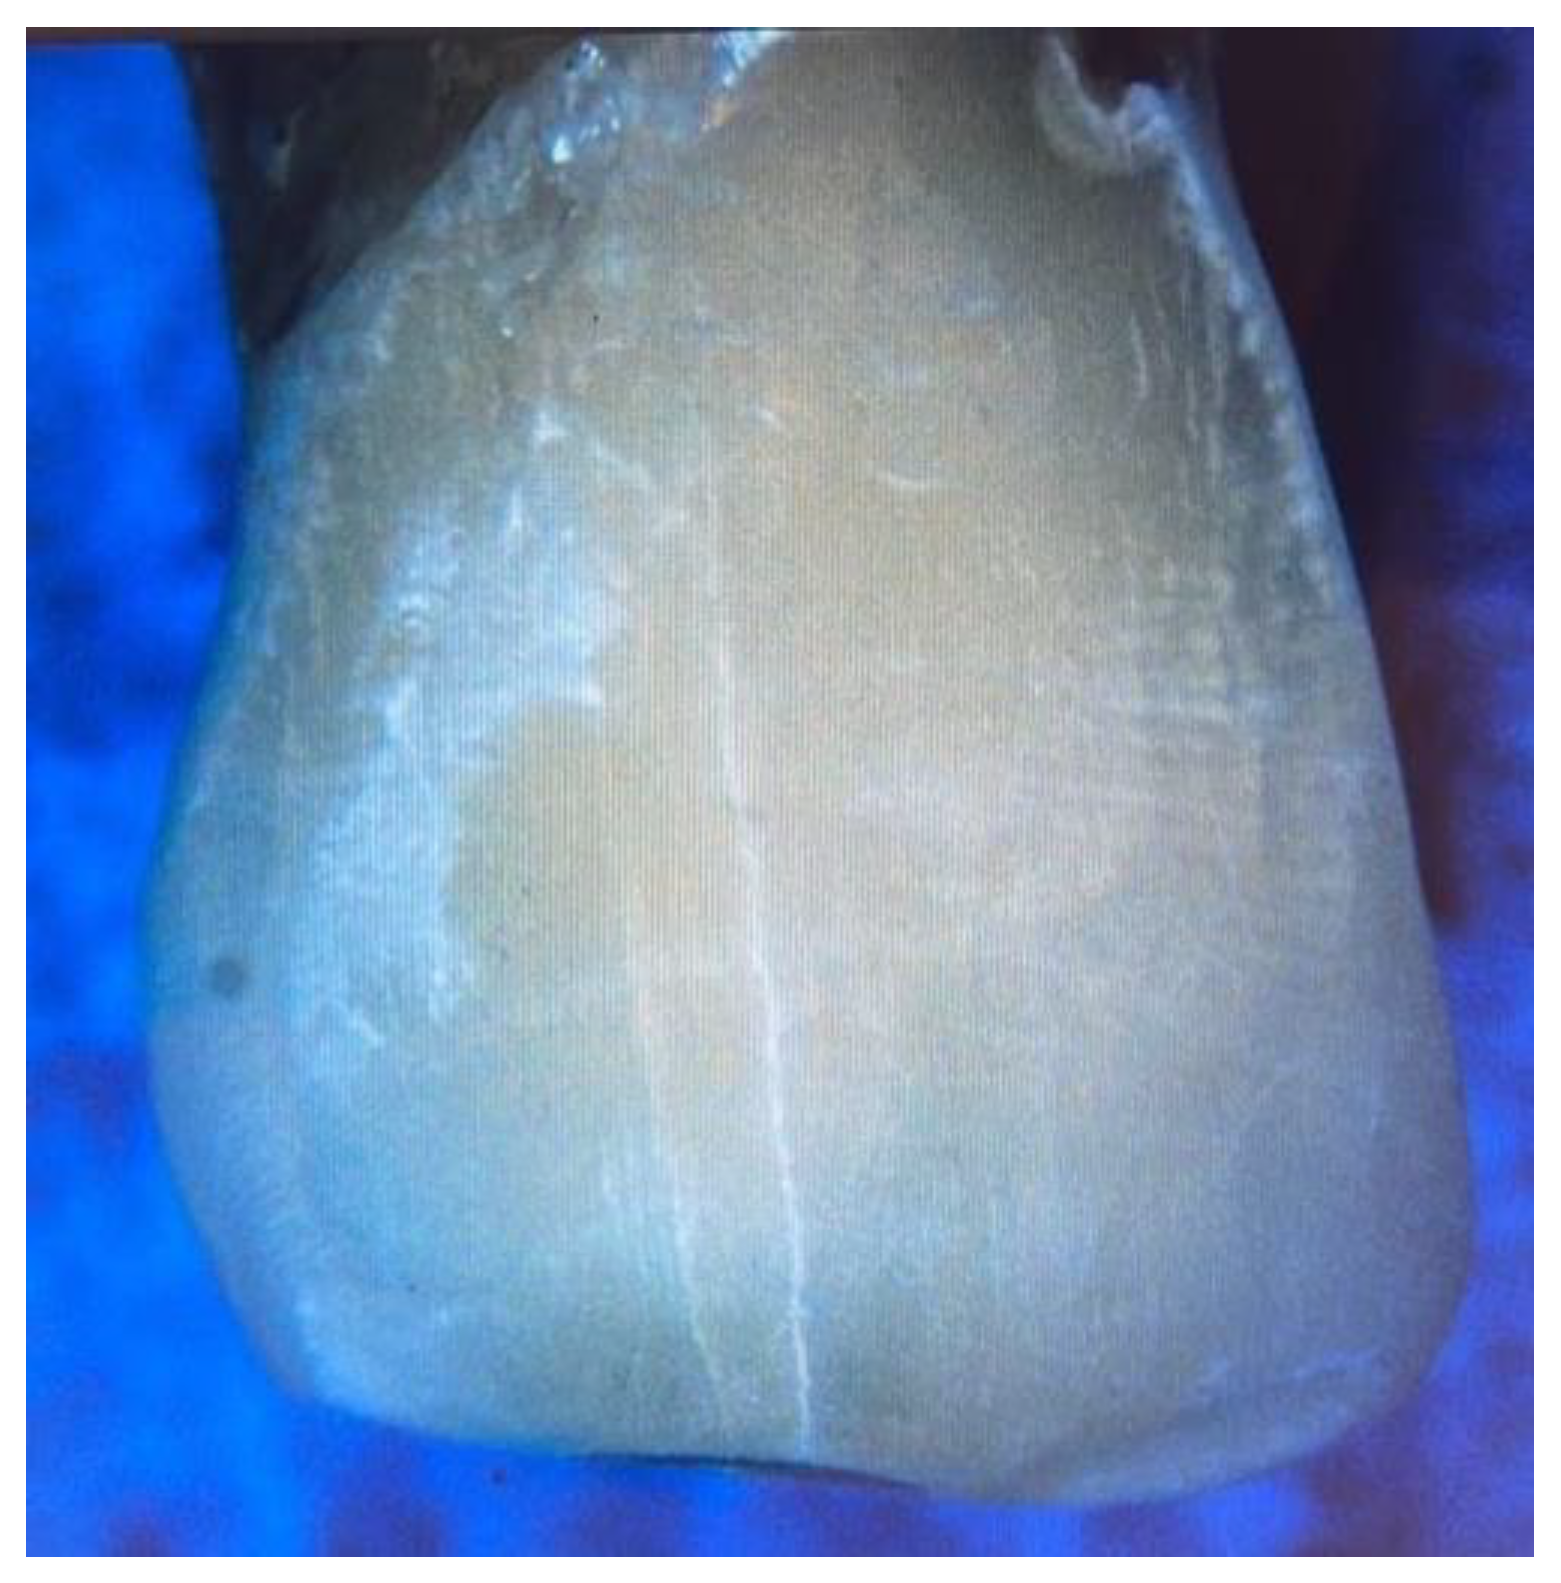

Figure 3. The microcracks formed after the metal orthodontic brackets debonding under the stereomicroscope.